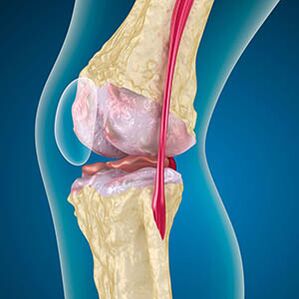

С артрозата хрущялът, облицоващ краищата на костите, е абразия или напълно отсъства. Повредената тъкан не е източник на болка, тъй като няма рецептори. Възпалението в близките структури причинява характерни симптоми.

Тялото продължава регенерацията на увредените тъкани, но хрущялът расте неравномерно. В резултат на това се образуват нередности, които нараняват други елементи на ставата. Характерът на остеофитите се обяснява с компенсация за гладък ставен хрущял. Друга версия показва, че растежът на "шпорите" Той е свързан с опит за стабилизиране на ставата медиално или странично поради отслабването на мускулите.